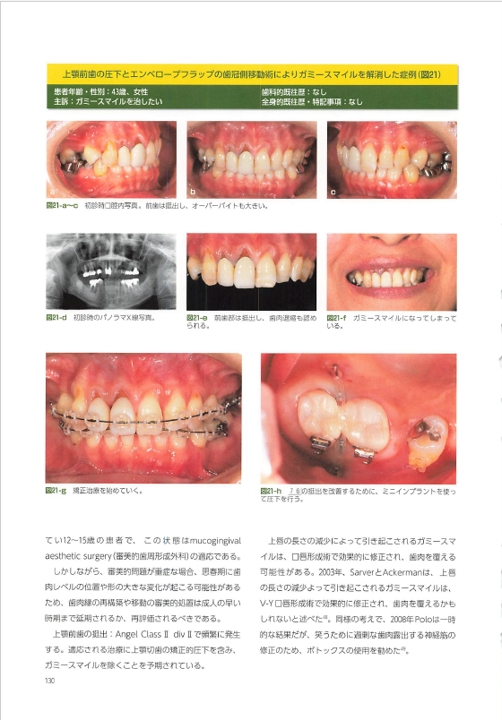

ニーズ3:40代以降で「歯周病が進行」している場合の矯正

40代~60代の方が矯正治療を希望されることも最近は増えてきました。お口の状態に問題がない場合は通常の矯正治療を行いますが、この年齢になると多くの方が「歯周病」になっていることが多くあります。歯周病の状態のまま矯正治療をすると矯正治療はうまくいかないため、まずは歯周病を改善してから治療を開始します。

また、歯周病の進行がかなり進行している場合、見た目も悪化しているため、そのまま矯正治療を行ったとしてもキレイにならないことがあります。そこで当院では、歯周病と矯正治療の他、セラミックの被せ物やケースによってはインプラントを併用し、お口全体の審美性を回復させる治療も行っています。

この総合的な治療を行うことで、口元が綺麗になる他、歯周病の再発防止(歯周ポケットを浅くする)、適切な噛み合わせの調整も可能になるため、お口全体の健康にもつながります。

このような治療は、当院の担当医である理事長はとても得意としています。このケースに関して、海外での発表や書籍の執筆も行っています。